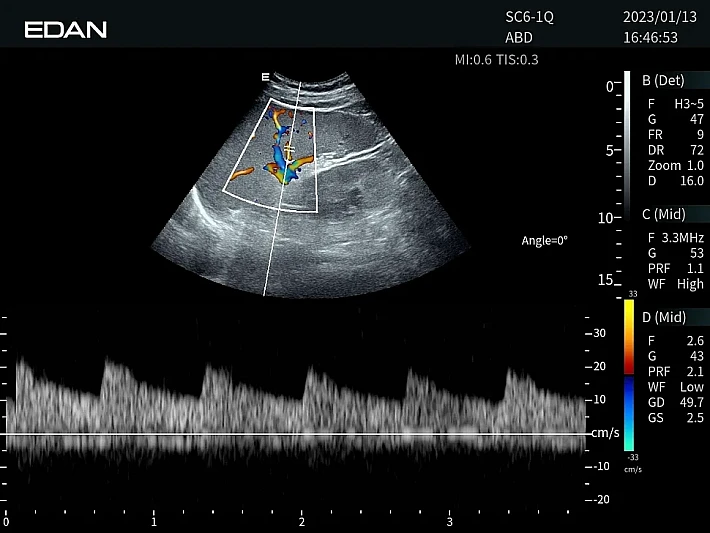

Медицинское оборудование и сервисное обслуживание